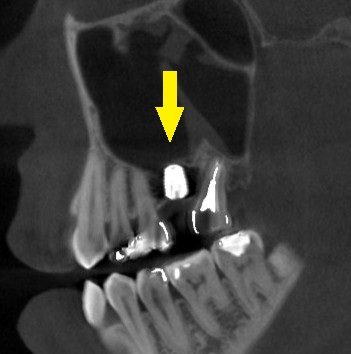

CTを撮影してみると、方向によっては、骨がありそうに見えますが、やはり十分な骨量とはいえませんでした。

ある程度の骨はありますので、ワイドインプラントを用いて、人工骨は使用せず、骨造成も行わないで、インプランント埋入が可能であると説明させていただきました。

ご納得いただけましたので、本日、ワイドショートインプラント、直径5.0mm、長さ7mmのインプラントを埋入しました。

下の写真、2段目が手術前のCT、3段目が手術後のCTです。